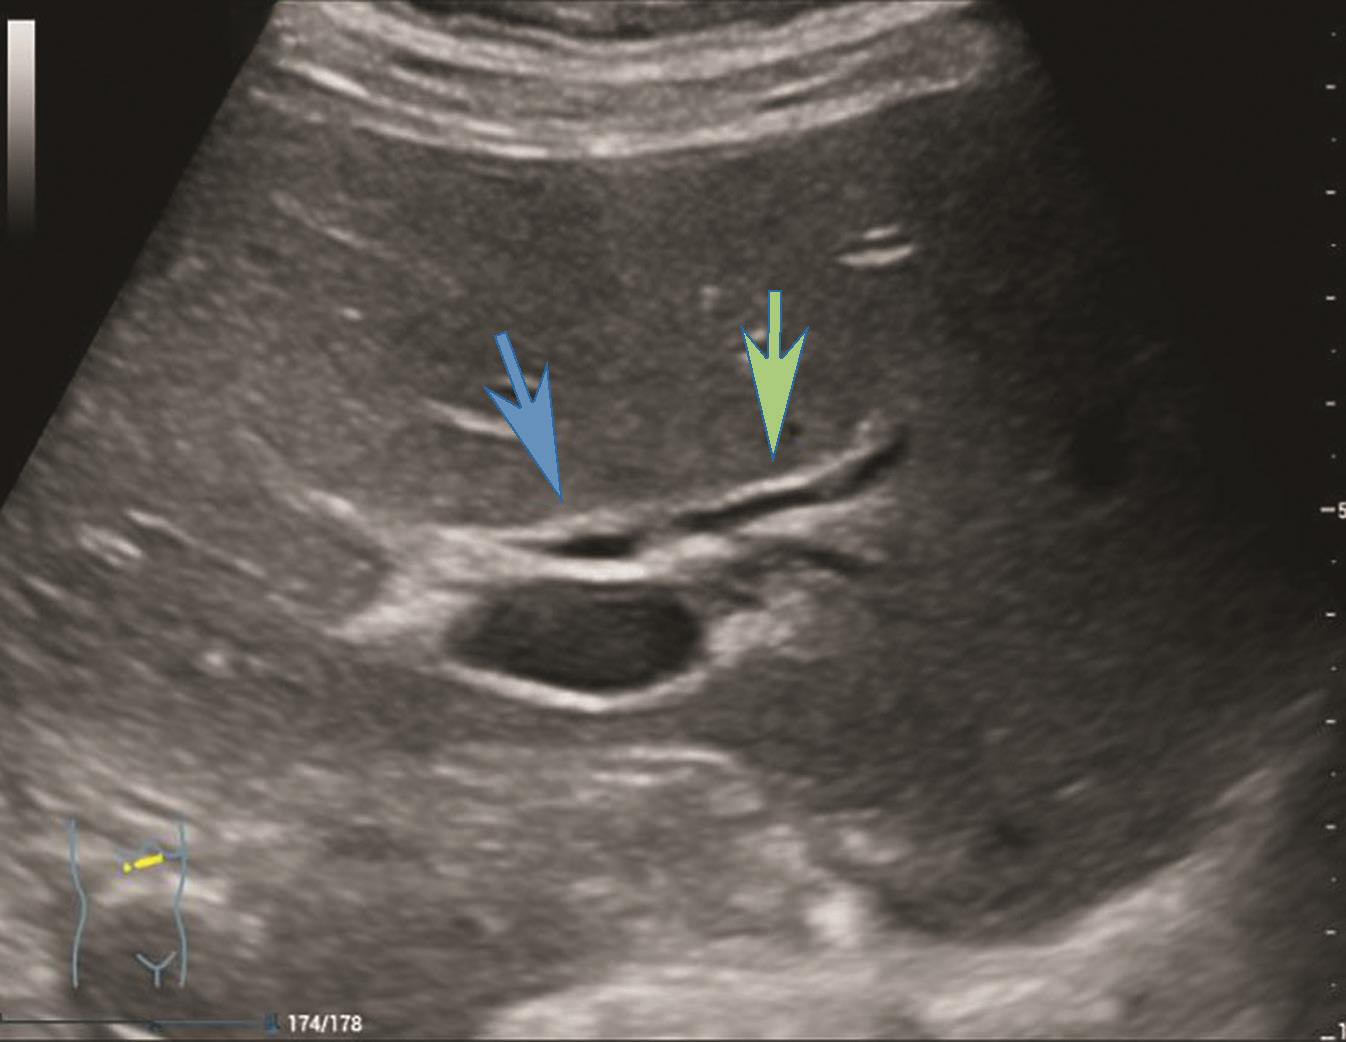

(3)左肝内胆管及门静脉横部前方左右肝管汇合处灰阶超声图像(图2-1-1)。

图2-1-1 左右肝管汇合处灰阶超声图像

图示蓝色箭头示右肝管,绿色箭头示左肝管